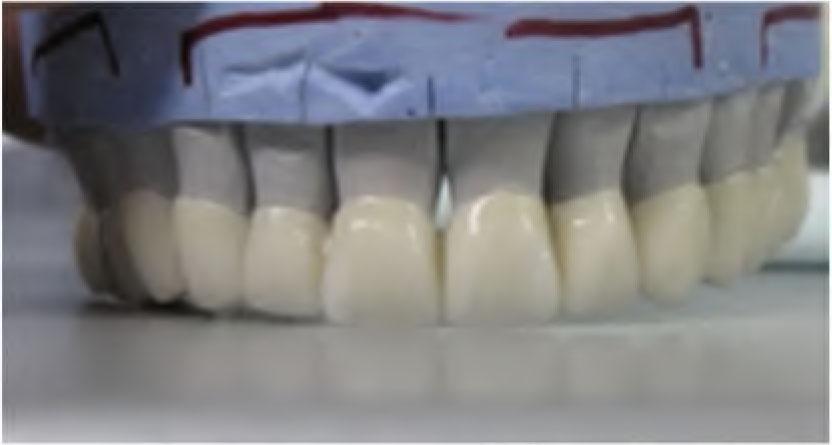

At the first stage of prosthetic rehabilitation, the proper VDO was determined by the Niswonger method (22). The distance between nose and chin tips was measured at the physiologic rest position and compared to the VDO at the centric relation position. The patient’s freeway space was 8–9 mm (difference between the physologic rest position and VDO). This method was verified with the closest speaking space method (23). Furthermore, the upper and lower impressions were made in alginate (irreversible hydrocolloid) and the diagnostic casts were poured in dental stone (type IV). The casts were mounted on semi-adjustable articulator (Bio-Art A7plus) using a standard face-bow record and an interocclusal record with occlusal registration material (Occlufast rock, Zhermack, Germany). The new VDO was set by approximately 4 mm increase in the incisal guidance pin of the articulator. We followed the rule called a 1:2:3 relationship (24). According to this rule, for each 1 mm that the VDO is increased vertically in the posterior region, the incisal pin of the articulator should be increased vertically by 3 mm. For this reason, the VDO was increased posteriorly by 1.3 mm and the incisal pin of the articulator was increased by 4 mm. Diagnostic wax-up was done at increased VDO and used for fabricating the provisional restorations. Then, the maxillary and mandibular teeth were prepared following principles of tooth preparation (25) with the shoulder of 1 mm wide as a gingival finish line. Provisional restorations were made using the over-impressions that were produced from the diagnostic wax-up. The provisional restorations were cemented with temporary cement (Temp-Bond, Kerr, Switzerland) and the patient’s adaptation has been monitored for 2 months (Figure 4).

Provisional restorations fabricated at the increased VDO